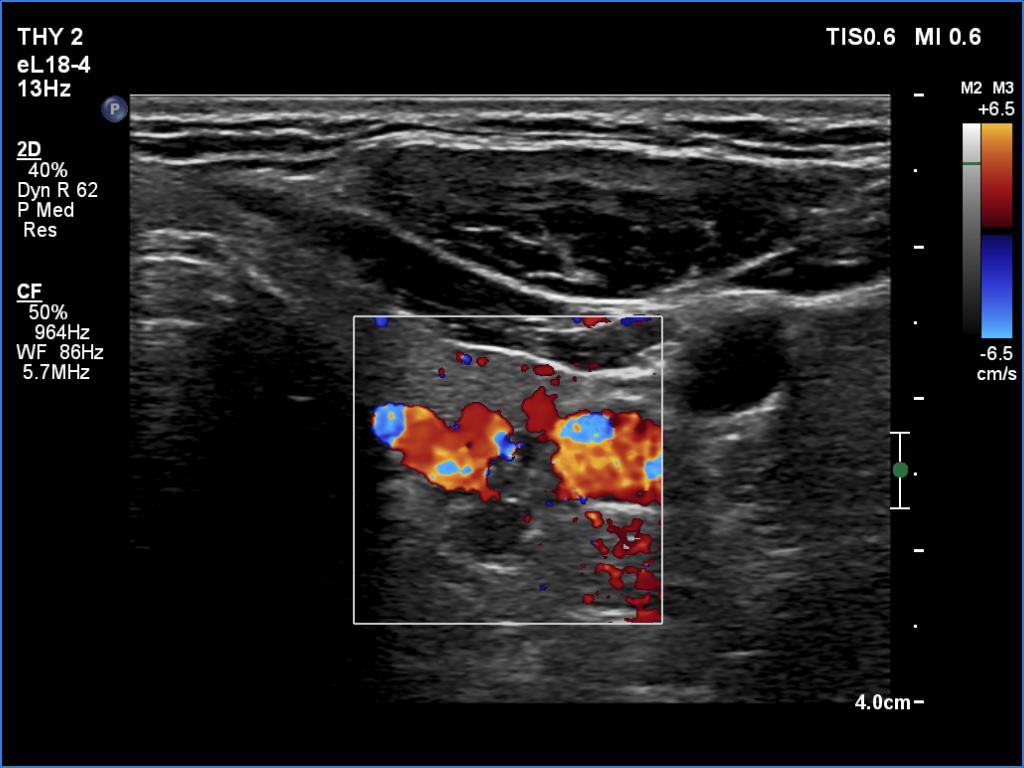

Ultrasonography. The thyroid was echonormal. There was a hypoechoic mass dorsal and under to the lower pole of the left thyroid lobe.

We tried to gain cytological material two-times from the mass but it was doubtful whether we reached the hypoechoic mass. Aspiration cytology was non-diagnostic. Wash-out parathormone was 0.1 pg/ml.